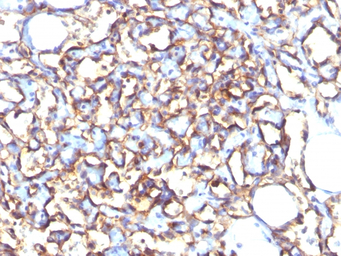

IHC-P analysis of human angiosarcoma tissue using GTX34977 PODXL antibody [3D3].

IHC-P analysis of human placenta tissue using GTX34977 PODXL antibody [3D3].